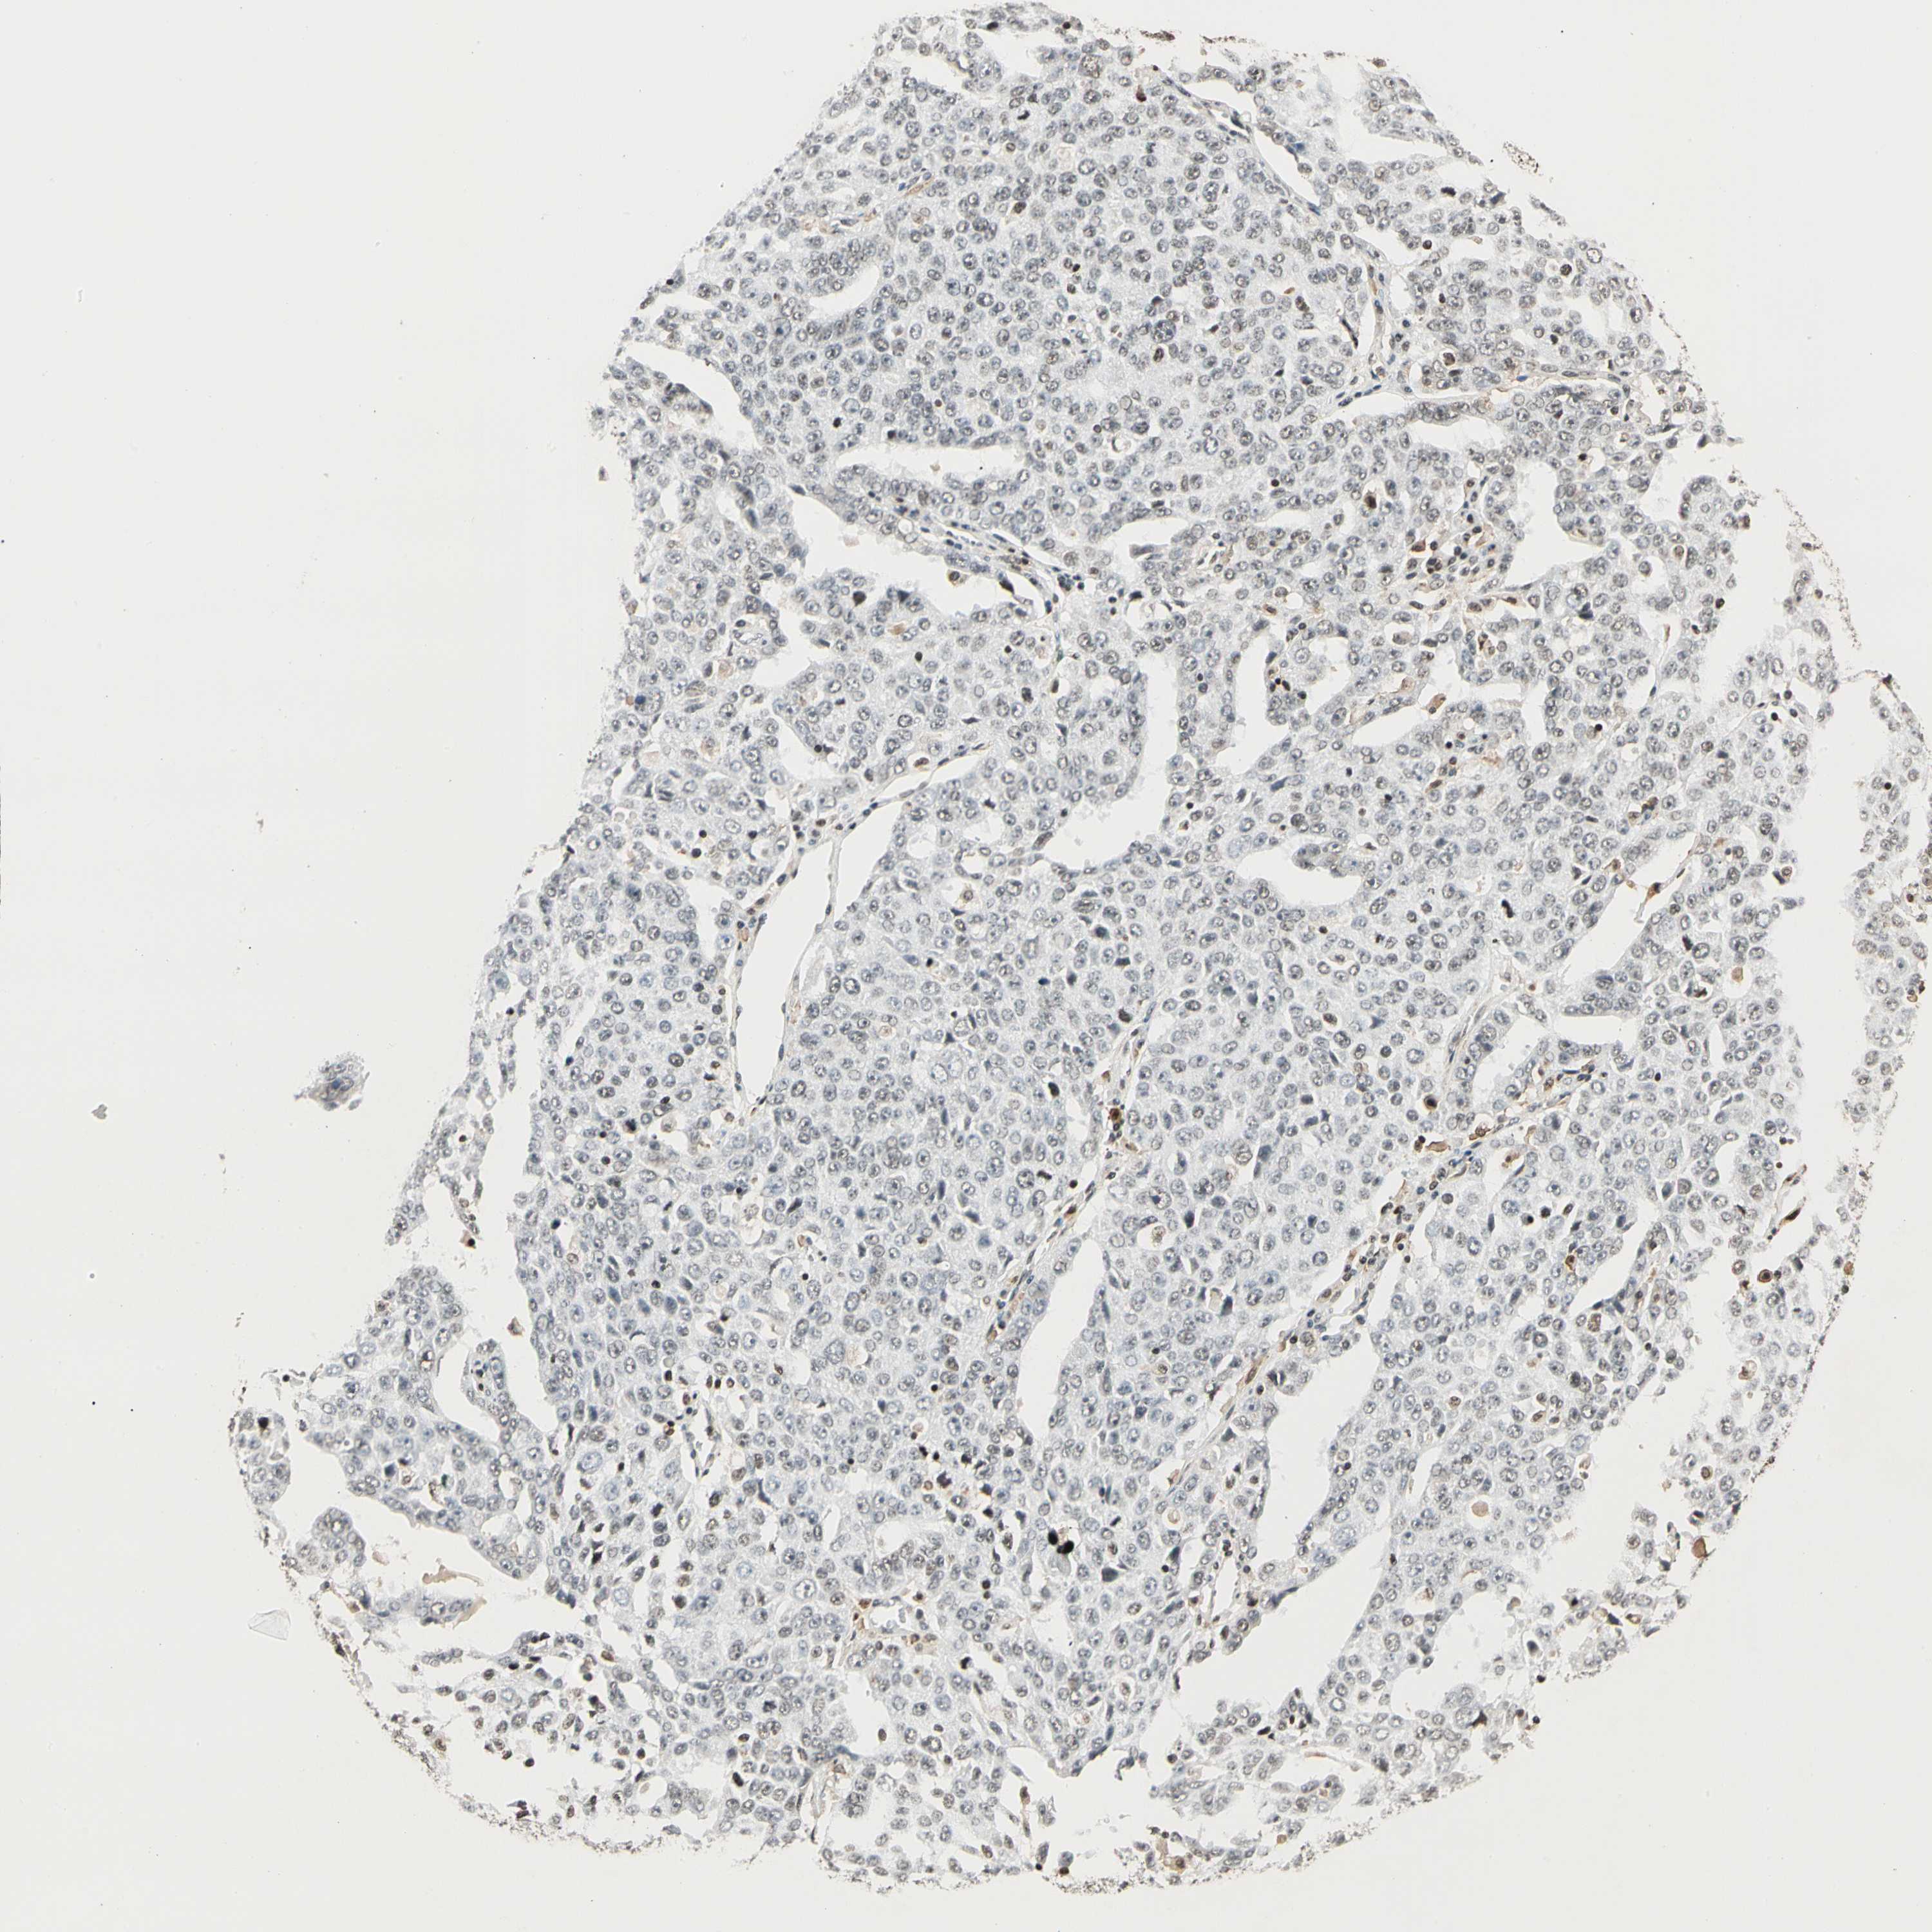

OVARIAN CANCER - Protein expressioni

A mouse-over function shows sample information and annotation data. Click on an image to view it in a full screen mode. Samples can be filtered based on level of antibody staining by selecting one or several of the following categories: high, medium, low and not detected. The assay and annotation is described here.

Note that samples used for immunohistochemistry by the Human Protein Atlas do not correspond to samples in the TCGA dataset.

Antibody stainingi

Antibody staining in the annotated cell types in the current human tissue is reported as not detected, low, medium, or high, based on conventional immunohistochemistry profiling in selected tissues. This score is based on the combination of the staining intensity and fraction of stained cells.

Each image is clickable and will lead to virtual microscopy that enables deeper exploration of all samples and also displays staining intensity scores, fraction scores and subcellular localization as well as patient and tissue information for each sample.

Antibody HPA007641

Antibody CAB022464

Staining

High

Medium

Low

Not detected

Intensity

Strong

Moderate

Weak

Negative

Quantity

>75%

75%-25%

<25%

None

Location

Nuclear

Cytoplasmic/membranous

Cytoplasmic/membranous,nuclear

Cystadenocarcinoma, serous, NOS

Carcinoma, endometroid

Cystadenocarcinoma, mucinous, NOS

Carcinoma, NOS